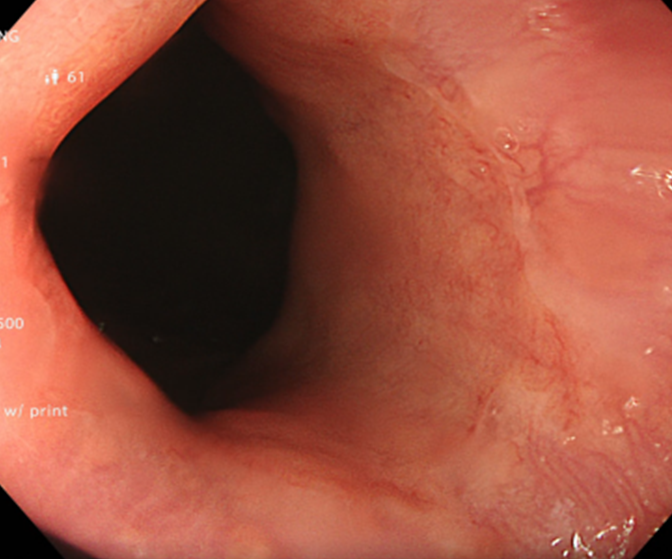

Kết quả nội soi dạ dày: Viêm teo niêm mạc dạ dày (C2 theo Kimura), dị sản ruột và có vi khuẩn H.pylori dương tính với test Urease từ mảnh sinh thiết qua nội soi.

Hình 1: Hình ảnh nội soi dạ dày